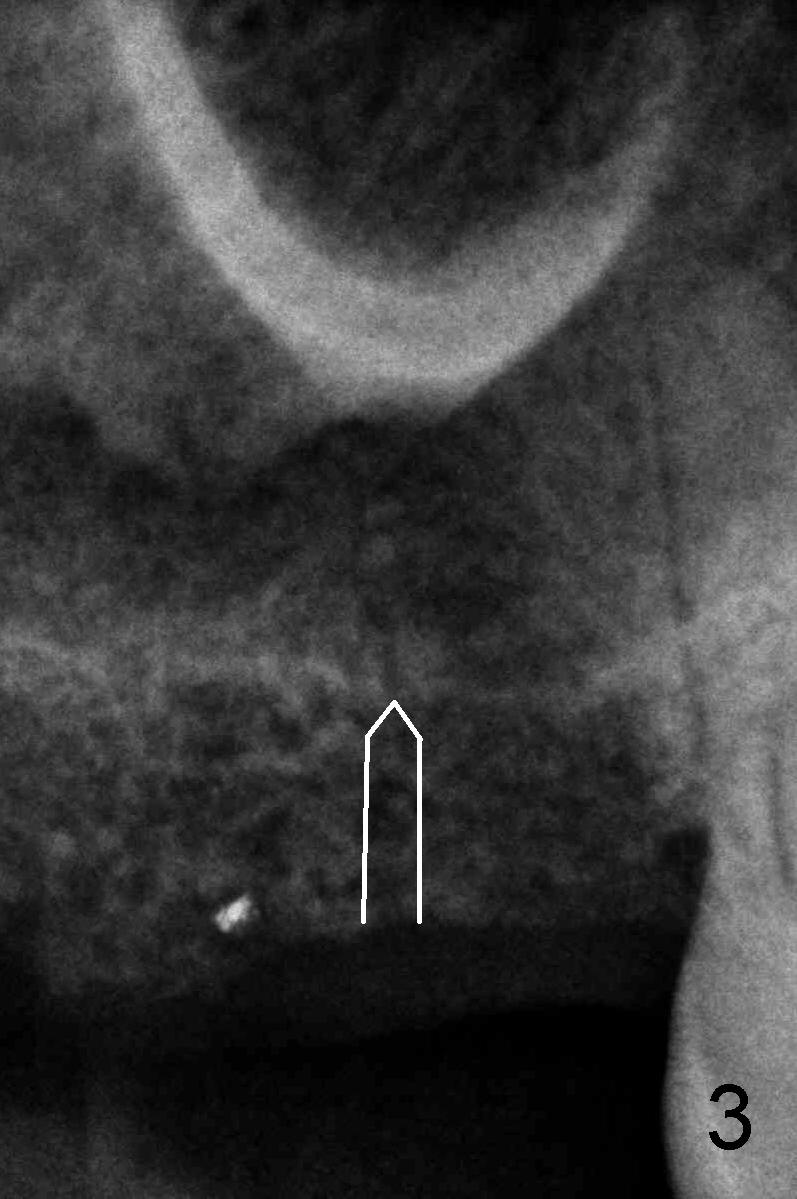

A 60-year-old man requests restoration of the missing upper right 2nd molar (Fig.1).  It appears that the bone height is limited (between white and red arrowheads, approximately 5 mm (Fig.5)).  Study of the sinus floor in association with the roots of the 1st molar reveals that the palatal root (P) appears inside the sinus.  In fact it is not.  Therefore there is bone apparently inside the sinus.

For the same reason, the root of the 2nd molar must have been above the sinus floor (Fig.2 arrowheads).  CBCT may confirm the fact.

Anyway, a 1.6 mm pilot drill or 2 mm osteotome may be used to initiate osteotomy at the depth of 4-5 mm (Fig.3).  An explorer is used to check whether the sinus membrane has been reached or not.  As the diameter of bone expanders or osteotomes increases, the depth of the osteotomy increases (Fig.4), pushing the native bone into the sinus.  Each step check sinus membrane integrity by using an explorer or doing nose blowing test.  The implant can also push more bone upward when it is being placed (Fig.5).  Combined lateral and crestal sinus lift is not recommended in this case because of limited access.